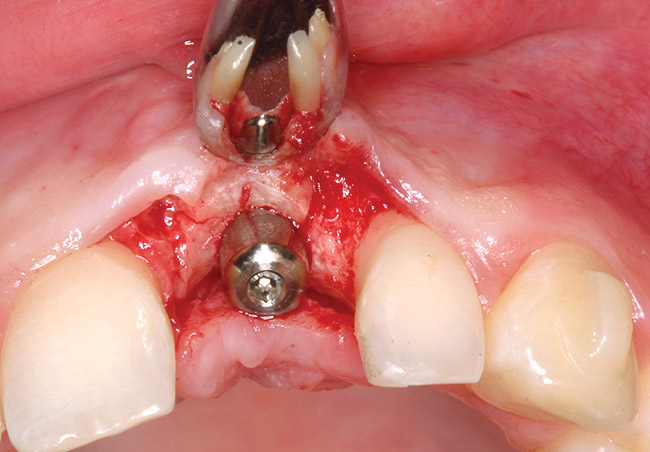

Treatment consisted of flapless extraction, socket grafting using mineralized bone allograft (Puros®, Zimmer Dental Inc, Carlsbad, CA), and a pedicled connective tissue graft36,37(Figure 11). Five months post-surgery, reentry was accomplished via a mid-crestal and labial sulcular incision. A crestal plasty was per- formed before implant placement into type II bone (Figure 12 and Figure 13). An immediate provisional was used for 3 months (Figure 14) before final crown fabrication (Figure 15).

Figure 11  Socket graft with mineralized allograft and pedicle connective tissue graft.

Figure 11

Figure 12  Stage I surgery (implant shown with healing abutment), 4 months after extraction and socket graft.

Figure 12